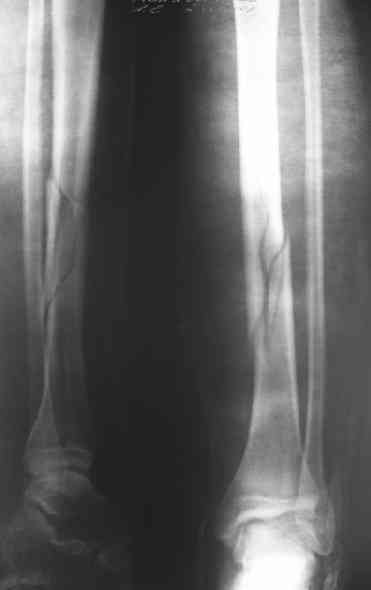

Дорогой Александр. Имею скромный опыт использования системы Fixion при переломах плеча, бедра и тибии. Всего 18 наблюдений с сентября 2006 г. Результаты отличные. Гвоздь индивидуален для каждого медуллярного канала. Легко имплантируется как в узкий, так и в деформированный канал. Это позволяет применять метод интрамедулярного остеосинтеза без ненужных потерь времени операции, флюороскопии и реально снижает крвопотерю и операционный риск. Удаление происходит без проблем. Особенно интересны больные с ипсилатеральными переломами бедра и голени.

Да, спасибо за интересные иллюстрации. Получилось очень симпатично. На большеберцовой кости непременно надо было винты? Там же был торцовый упор, перелом в средней трети?